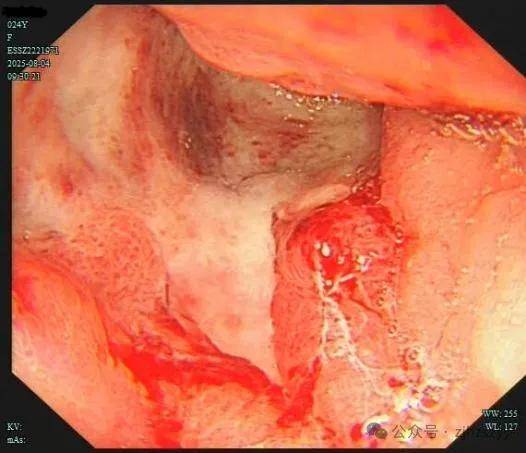

直到她开始频繁出现黑便,并在片场拍戏时几次呕血,才被同事紧急送往我院急诊。情况紧急,医生立即为小雯安排了急诊胃镜检查,发现她整个胃窦被一巨大的溃疡占据,黏膜组织变得僵硬、缺乏弹性,好似“皮革”一般。而随后的活检结果,更是给了这个年轻姑娘沉重一击——胃印戒细胞癌。

胃印戒细胞癌早期的隐匿性很强,在胃镜下表现也不明显,识别非常困难,可能表面看起来只是点、片状糜烂,而实际上已经多点生长。